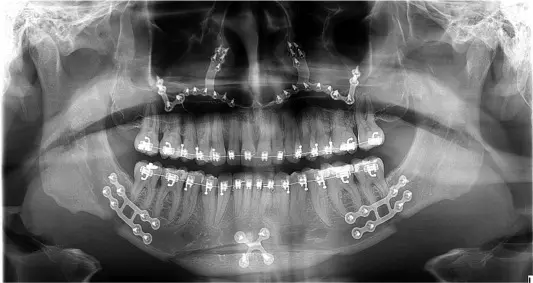

3. جراحی فک: جراح فک و صورت موقعیت استخوان فک را اصلاح میکند تا هماهنگی بهتری ایجاد شود.

4. ارتودنسی بعد از جراحی: برای تکمیل درمان و تثبیت نتایج، تنظیمات نهایی دندانها انجام میشود.

برخی از ناهنجاریهای فکی و دندانی تنها با ارتودنسی قابل اصلاح نیستند و نیاز به ترکیب آن با جراحی فک دارند. این روش که به ارتوسرجری معروف است، برای بیمارانی که مشکلات شدیدی در موقعیت فکها دارند، توصیه میشود. ارتودنسی قبل از جراحی، دندانها را در موقعیت مناسب قرار میدهد و پس از جراحی، تنظیمات نهایی انجام میشود تا فک و دندانها هماهنگ شوند.